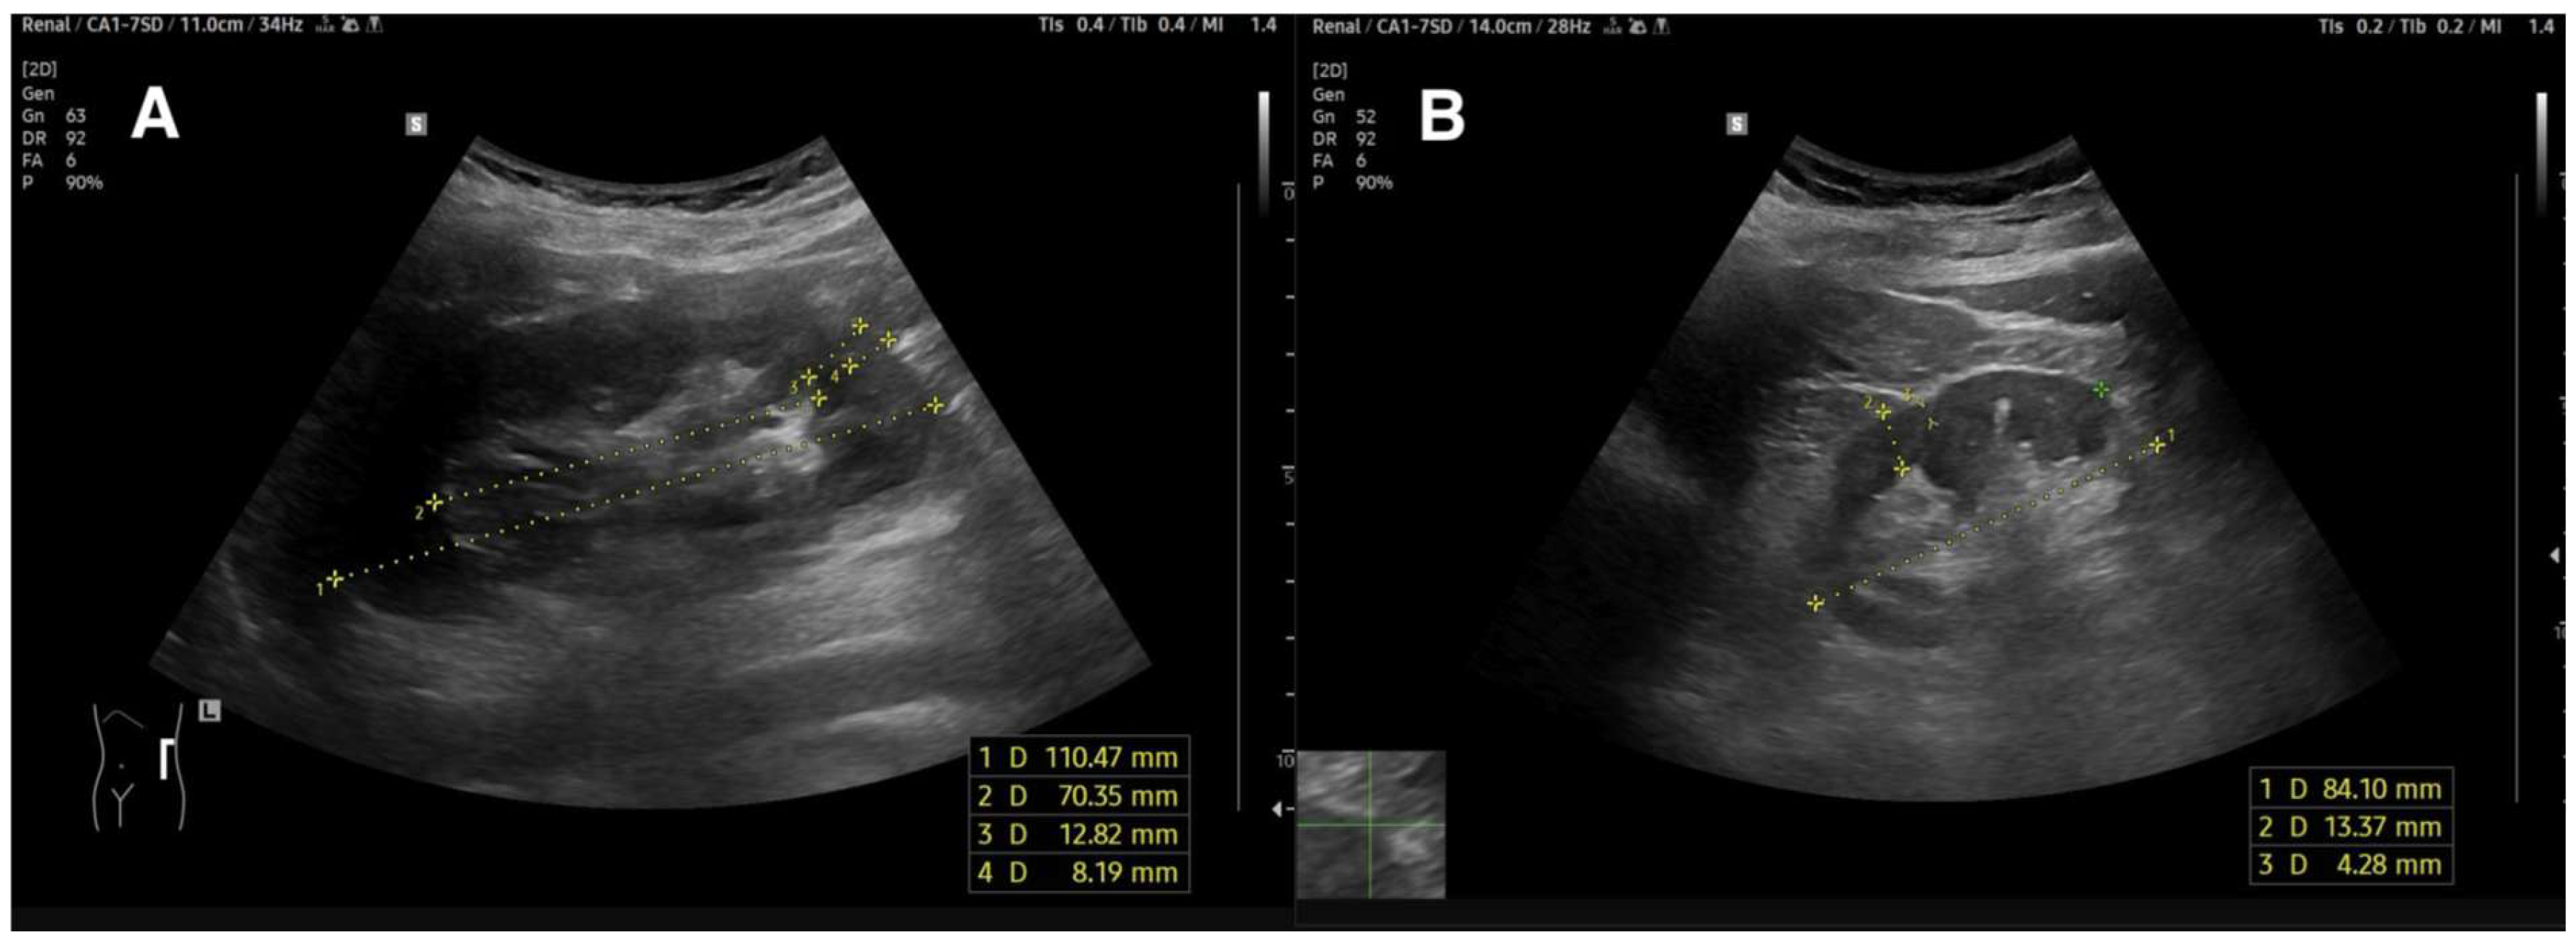

3.1.2. Renal Length

3.1.3. Cortical and Parenchymal Thickness